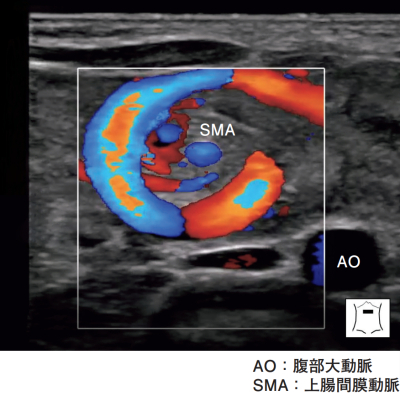

血液所見:赤血球 560 万、Hb 18.5 g/dL、Ht 48 %、白血球 11,000、血小板 18 万、PT-INR 1.0(基準 0.9~1.1)、APTT 30 秒(基準対照32.2)。血液生化学所見:総蛋白 6.8 g/dL、アルブミン 4.0 g/dL、AST 40 U/L、ALT 10 U/L、クレアチニン 0.5 mg/dL、Na 135 mEq/L、K 4.0 mEq/L、Cl 98 mEq/L、尿素窒素 7.0 mg/dL。CRP 0.1 mg/dL。上部消化管造影検査で十二指腸より先に造影剤が通過しなかった。注腸造影像と腹部超音波像(カラードプラ)を別に示す。